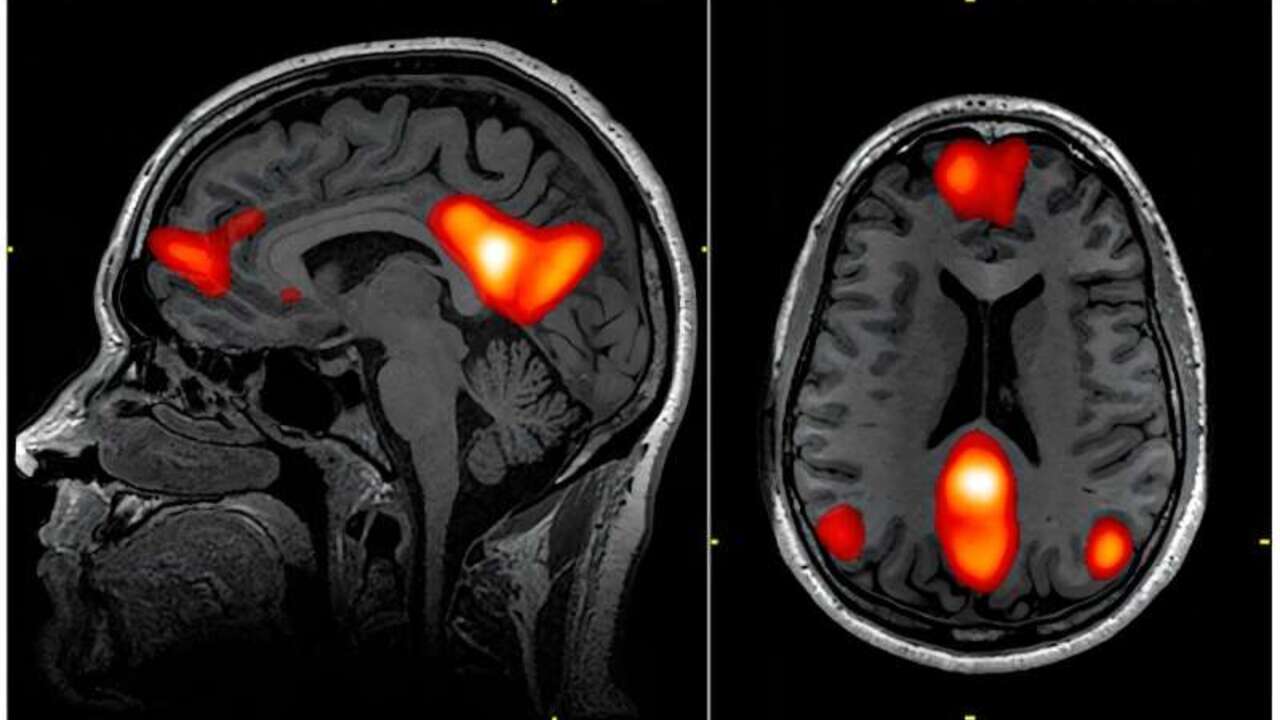

When we feel in trouble, our mind contains certain brain networks. Attention network attention is activated when we start watching a movie, for example, when you start watching a movie. As our interest is lost, the activity in the network of attention decreases. The same reduced activity is observed at the forefront or in the administrative control network due to its struggle to maintain involvement in indifferent content.

At the same time, the default network is activated by moving our attention to thoughts and reflecting itself.